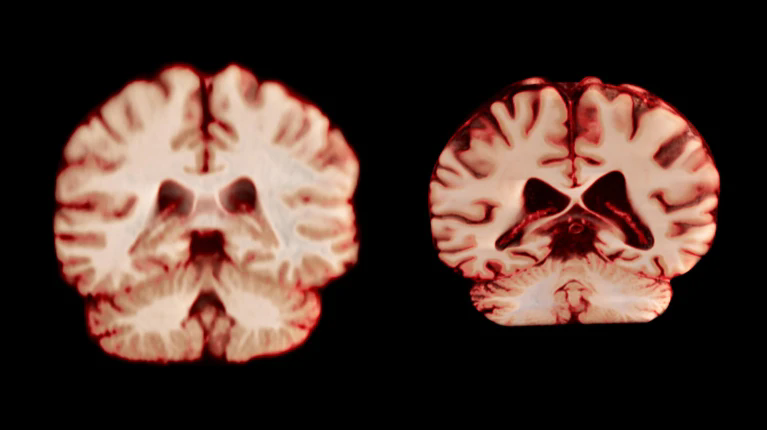

健康大脑(左)和患有阿尔茨海默病的大脑。图片来源:Anatomical Travelogue/SPL